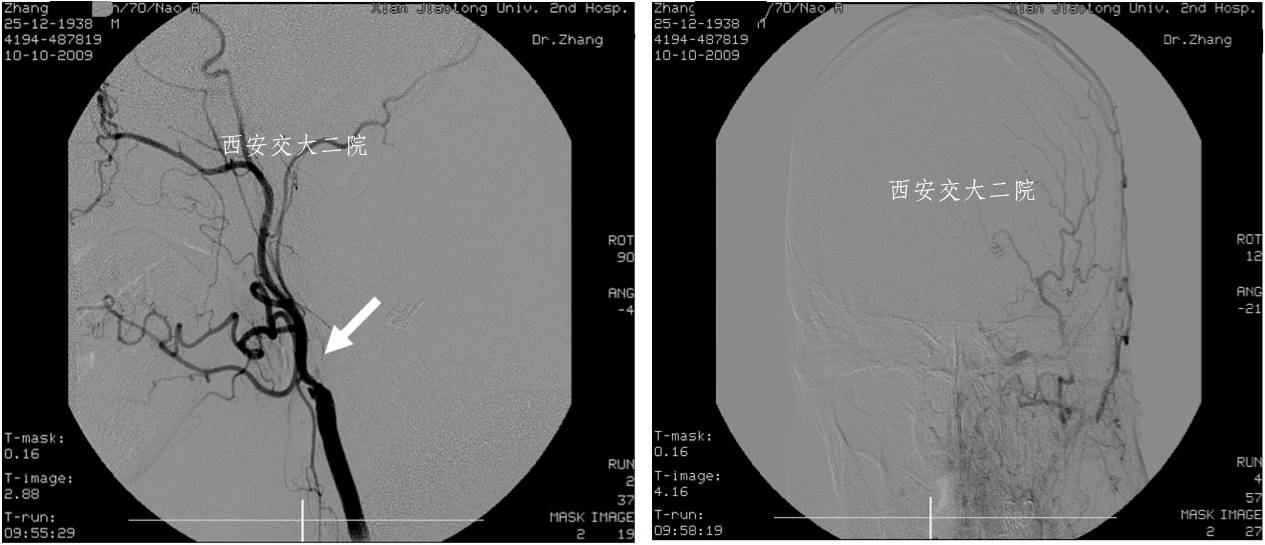

Case 1 颈内动脉C1段急性闭塞(2009年)

》男,70岁,突发右侧肢体无力3小时,DSA提示左侧颈内动脉起始段闭塞。